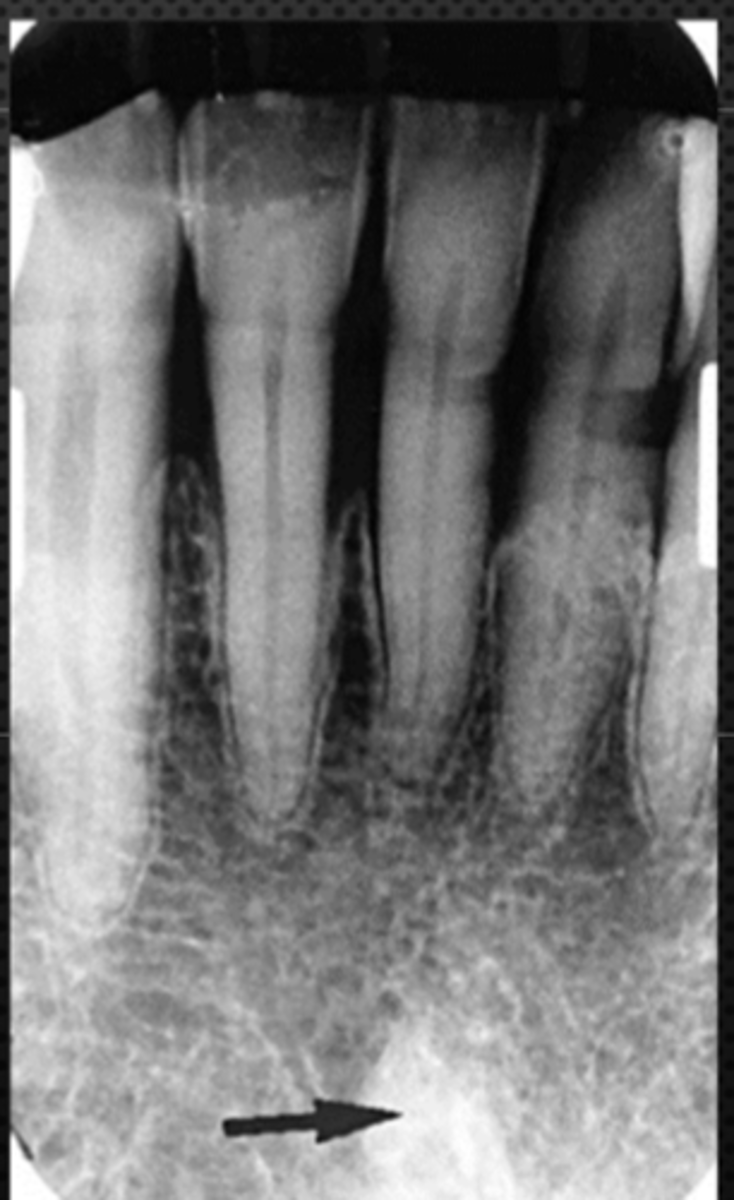

Mandibular canal

Identify the structure

Identify the radiolucent structure

Nutrient canals (neurovascular canals)